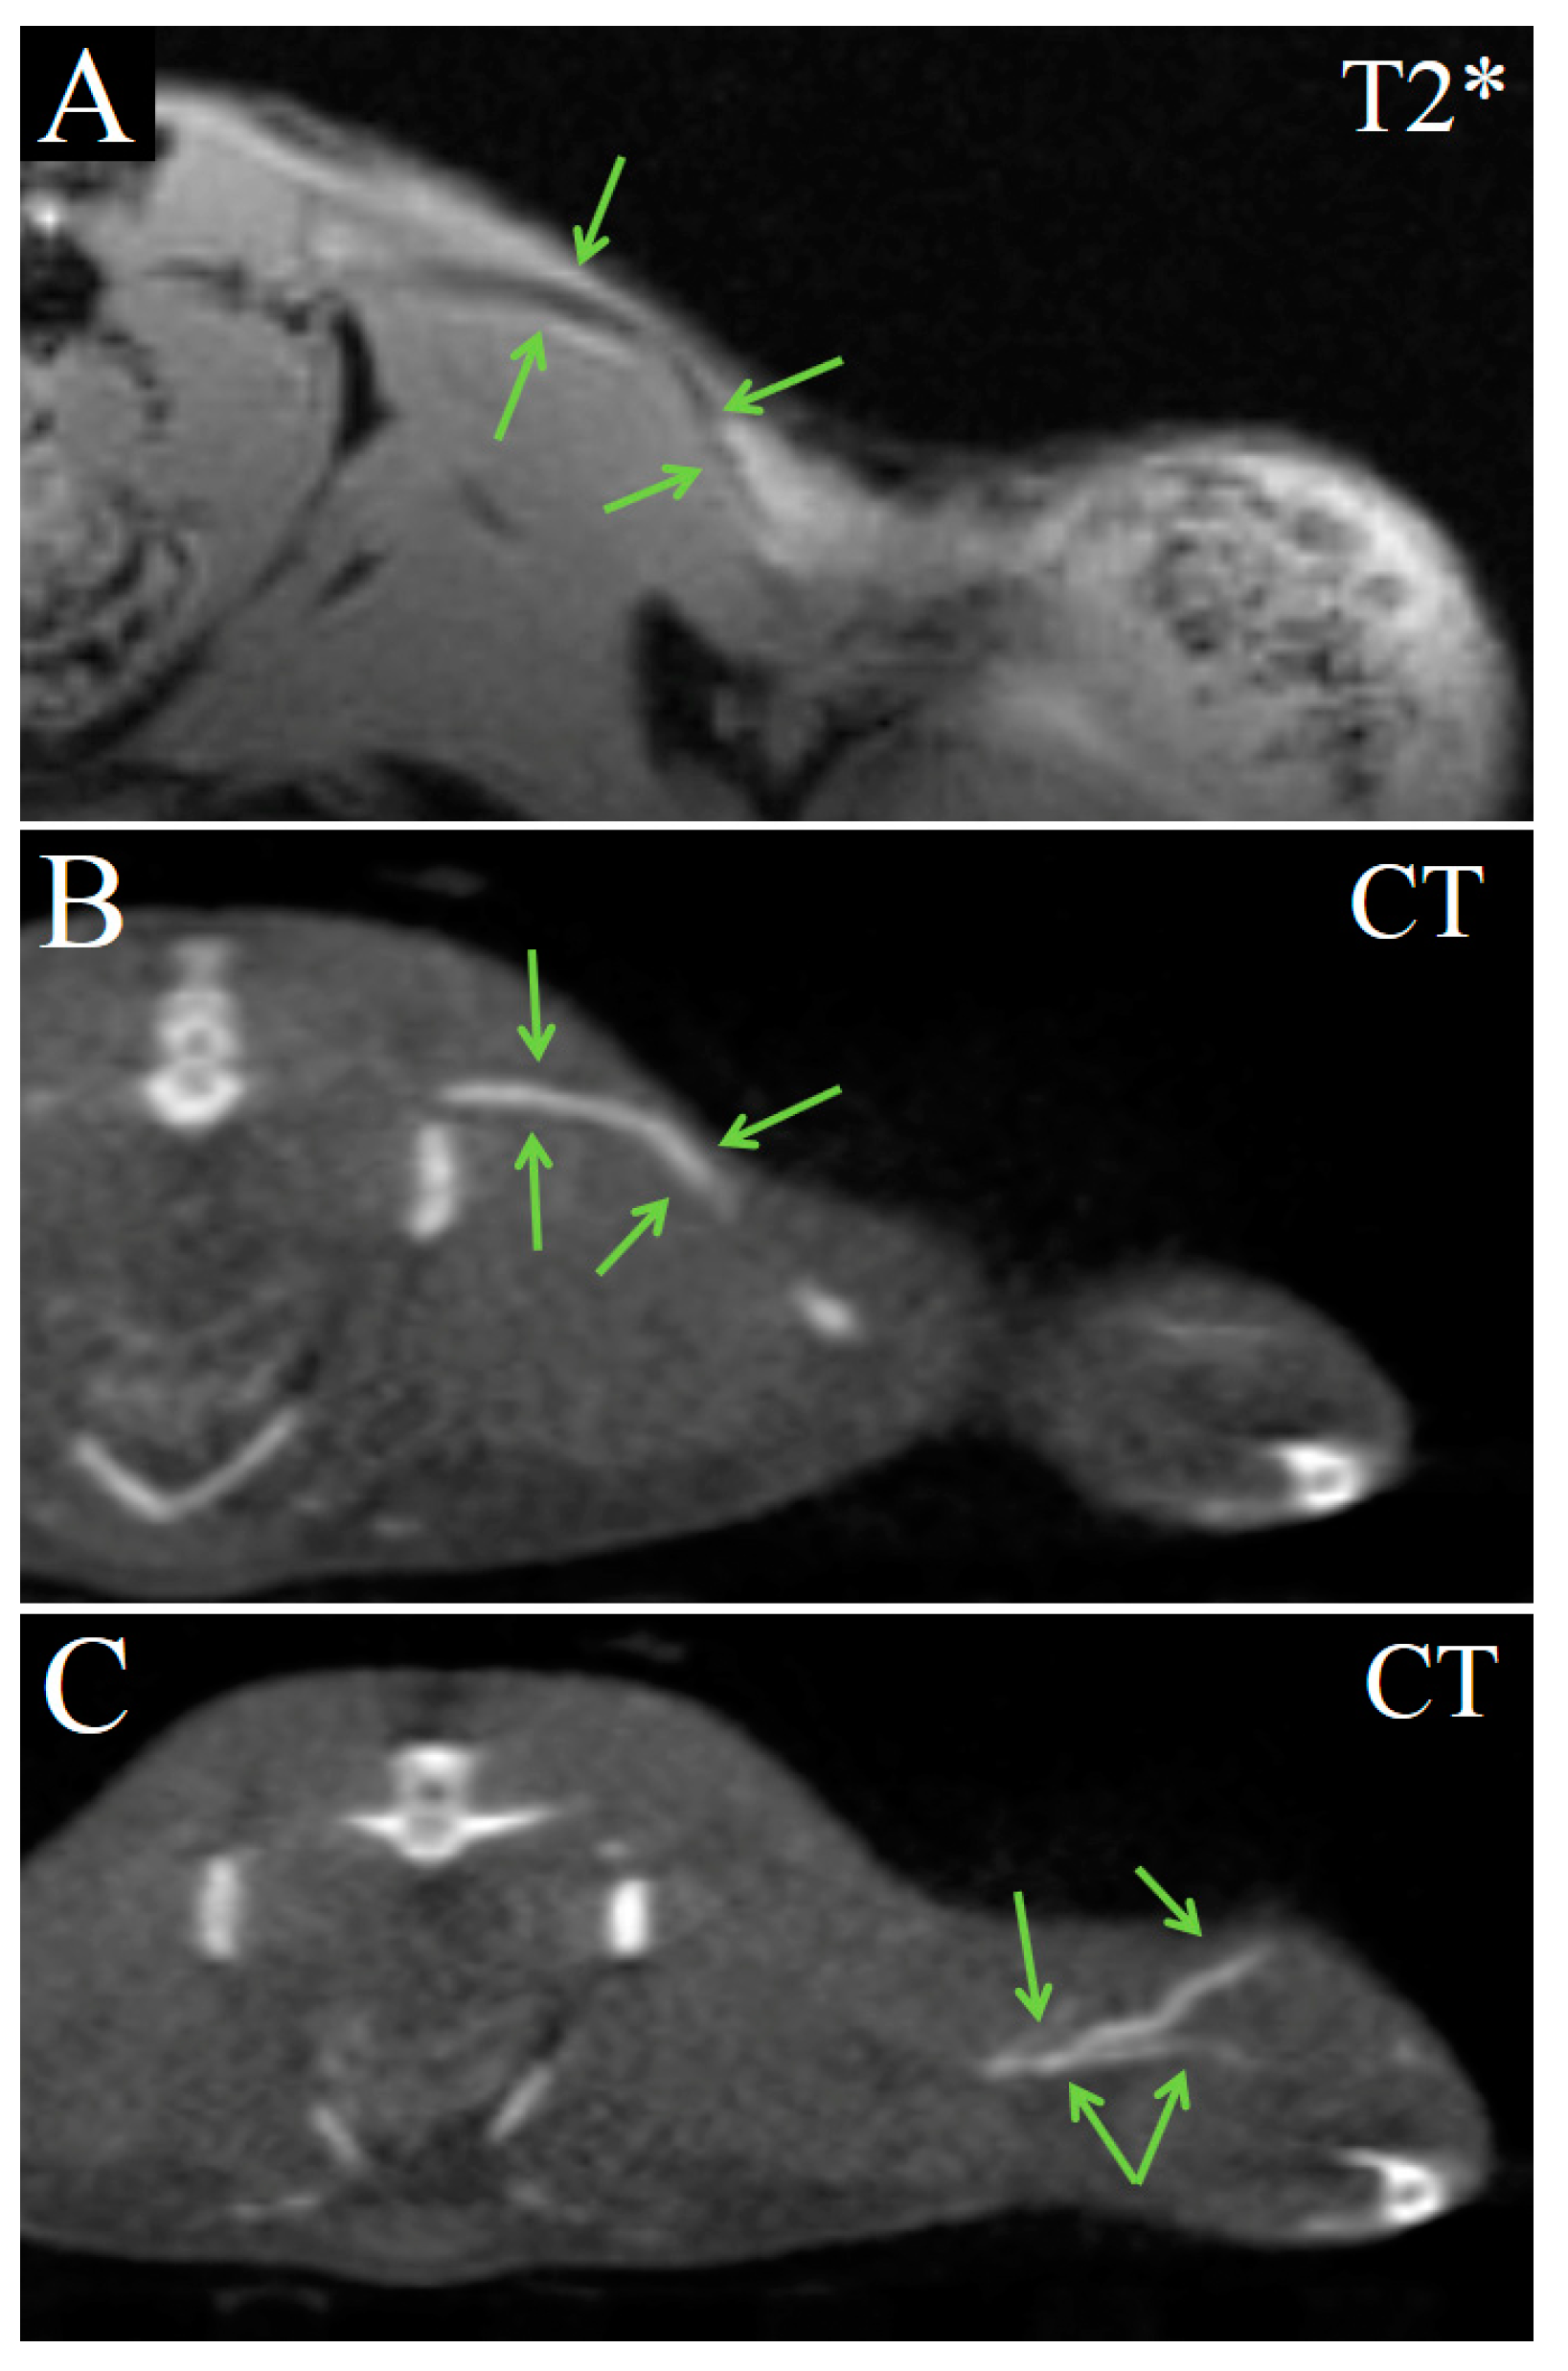

Enhanced lines in the inner periphery, related to the tumor capsule, vaguely demarcated the tumor from the adjacent muscles (Figure 7). The subcutaneous part of the tumor capsule avidly accumulated contrast agent, and became strongly hyperdense in CT (Figure 7B).

Figure 7.

Coronal images of Ca755 mammary carcinoma. (A) T2*MRI 16 min post injection of Fe3O4@Au; (B) CT image 22 min post injection of Fe3O4@Au. Enhanced lines in the inner periphery (related to the tumor capsule) distinguish the tumor from adjacent muscle.

Starting from 50 min after injection, the contrast-enhanced region enlarged and occupied most of the tumor volume (Figure 8). This indicates that more nanoparticles extravasated and accumulated in the tumor tissue. Enhanced areas became more hypointense in T2*-weighted MRI images and more hyperdense in CT images (Figure 8).

Figure 8.

Transversal images of Ca755 mammary carcinoma. (A) T2 MRI 50 min post injection of Fe3O4@Au; (B) T2* MRI 50 min post injection of Fe3O4@Au; (C) CT image 65 min post injection of Fe3O4@Au. Arrows mark the enhanced area of the tumor.

On the 17th day post injection, the tumor volume significantly increased and contained necrotic areas, which were hypointense in T2- and T2*-weighted MRI and could hardly be distinguished from contrast-enhanced areas (Figure 9A,B). In CT images, the tumor’s structure remained homogenous, and areas of nanoparticle accumulation were easier to recognize (Figure 9B,C). Nanoparticles were located mostly in connective tissue septa and tumor capsules. Most likely, such a specific pattern formed due to the absorption of the nanoparticles by tumor-associated macrophages, with the subsequent migration of these cells to the capsule and accumulation within. Contrast-enhanced areas in the tumor became enlarged, but only minimally hyperdense and vague, without precise margins. The decrease in tumor tissue’s radiodensity was possibly related to enlargement of the tumor volume and, thus, to a decrease in nanoparticle concentration. Blood vessels did not contain any contrast agent at 17 days, all over the mouse body.

Figure 9.

Images of Ca755 mammary carcinoma at 17 days post injection of Fe3O4@Au. (A) T2 MRI, coronal image; (B) T2* MRI, coronal image. Blue arrows mark necrotic regions; (C) CT, coronal image; (D) CT, transversal image. Orange arrows indicate the connective tissue septa, green arrows indicate the area of nanoparticle accumulation.